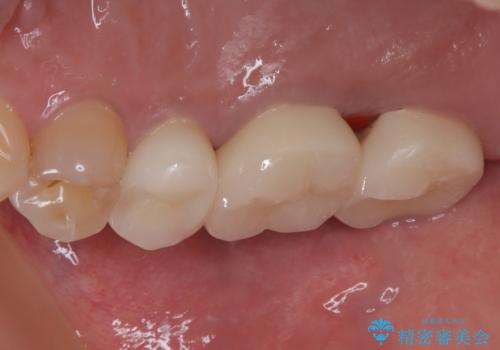

不快感の強い奥歯 オールセラミッククラウンでのむし歯治療

- とにかく奥歯に不快感を感じるとのことで来院された患者様です。

神経近くにまで及んでいる大きなむし歯や、歯肉の中深く、骨の近くにまでむし歯が進行している歯など、問題の多い状態でした。

神経を温存するための処置や、歯肉深くにまで及んだむし歯を改善するための歯周外科処置などを行っていき、オールセラミッククラウンにて補綴治療を行うこととしました。

術前の診断では神経が温存できるか否か、際どい状況でしたが、治療開始前の海外への帰省の際に自発痛(何もしなくてもズキズキ痛む)の症状が出てしまい、根管治療が必要となってしまいました。